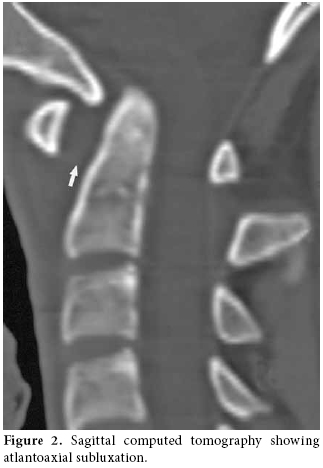

The lateral view of the cervical radiography revealed atlantoaxial subluxation (figure 1). On the computed tomography (CT), the distance between the axis and dens clearly widened as it measured approximately 10 mm (figure 2). The T1-weighted magnetic resonance imaging (MRI) showed a widened atlantodental space (figure 3a). At this localization, T2-weighted images revealed a heterogeneous hyperintense lesion, and at C2, C3, and C4 levels increased retropharyngeal soft tissue thickness appeared (figure 3b). In postcontrast T1-weighted sequences, the increased retropharyngeal soft tissue thickness and lesion showed heterogenous enhancement which was interpreted as soft tissue infection and abscess, respectively (figure 3c).

Radiological investigation plays an important role in the diagnosis. Plain anteroposterior and lateral radiographs may show asymmetry of the facet joints and increased predental space.[8] Both CT scanning and MRI are diagnostically used.[10] In our case, retropharyngeal soft tissue swelling was demonstrated. Dynamic studies may be necessary, but they may cause neurological complications.[14]

Subluxation of the atlantoaxial joint is graded using the classification system developed by Fielding et al.[17] The atlas is rotated on the odontoid, and there is no anterior displacement of the atlas in type I. In type II, the atlas is rotated on one lateral articular process with 3 to 5 mm of anterior atlas displacement. Type III consists of rotation of the atlas with anterior displacement greater than 5 mm. Type IV is characterised by rotation and posterior displacement of the atlas. Our case was classified as Fielding type III. The first step of the treatment is medical. The main goals of the therapy are a bacteriological cure, bone stability, and neurological treatment.[14] Intravenous antibiotics should be started for a minimum of four weeks, and there are strong recommendation for six weeks. As the grade of subluxation increases, surgery as a treatment becomes more necessary. In a more recent review by Wietzel, the authors suggest treatment of type I with a soft collar, type II with a hard collar, type III with a halo fixation, and type IV with open fixation.[16] Surgery is indicated only in cases of failed conservative treatment, recurrences of the subluxation, and for irreducible subluxations. Neurosurgical intervention usually involves open reduction of the deformity, and cervical fusion with a bone graft. Based on the clinical and radiological findings, we diagnosed the patient as having Grisel's syndrome and treated him with intravenous antibiotics and internal immobilization.